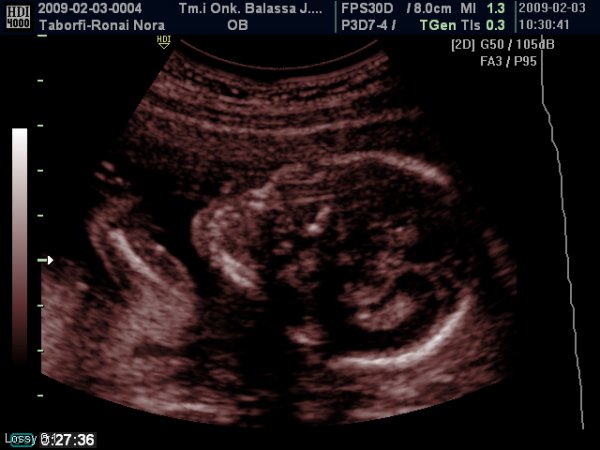

A lényeg, hogy rendben van az ultrahang és jól viselkedik a kiscsaj!